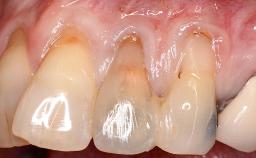

GBR and Soft-Tissue Augmentation Following Explantation to Rehabilitate a Soft- and Hard-Tissue Defect

It is sometimes necessary to remove and replace compromised implants. This case is a clear example of the need for multiple steps to achieve an optimal therapeutic result for patients with non-salvageable implants. It illustrates how the lost soft and hard tissues were rebuilt in a sequence that improved the healing of the hard tissues and assured their long-term stability. The 35-year-old healthy patient presented with clinical attachment loss on the proximal and lingual surfaces of the natural dentition. Some gingival recession was present on natural teeth, particularly in the posterior sextants (S1, S3, S4, and S6).